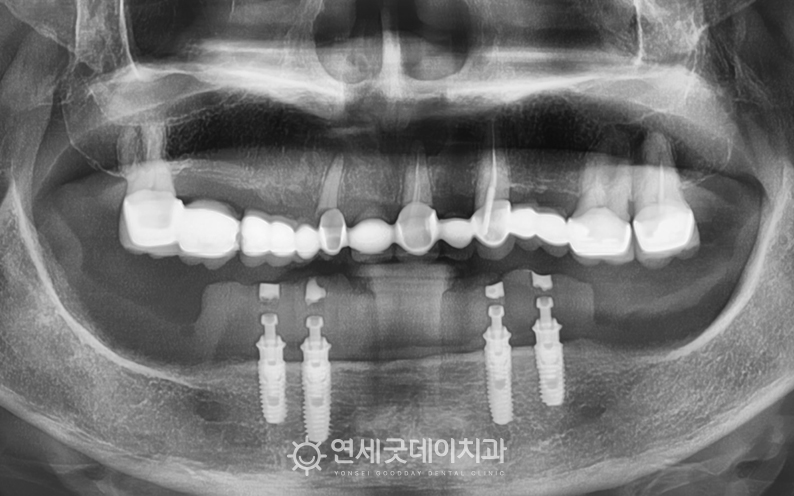

▲ 치료 전 구내모습 (촬영시기 : 2025년 11월)

하악의 경우, 임플란트 틀니를 사용하고 계셨으며

상악은 치아의 파절, 뿌리쪽 염증이 관찰되며

전체적인 구강 건강이 매우 좋지 않은 상태셨습니다.

▲ 하악 틀니 제거 (촬영시기 : 2025년 11월)

임플란트 틀니를 제거하니 고정하던 금속 바(bar)가 드러났으며

하악 잇몸뼈는 대부분 소실되어 높이가 거의 남아있지 않는 상태였습니다.

금속 바는 하악에 식립한 임플란트를 서로 연결해 놓은 구조로

구조물 위로 틀니를 끼워 고정하는 방식입니다.